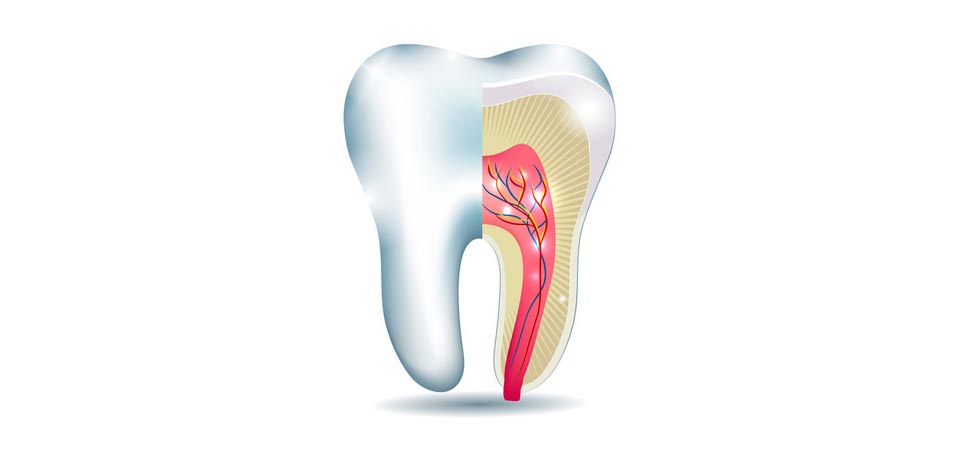

H γνώση και ευαισθητοποίηση για τη σημασία και την αξία της διατήρησης της ζωτικότητας του δοντιού μάς οδηγεί, ΣΗΜΕΡΑ, σε μία πιο συντηρητική-αναγεννητική αντιμετώπιση των παθήσεων του πολφού. Έτσι, σε περιπτώσεις μεγάλου τερηδονισμού ή τραυματισμού δοντιού, στοχευόμενα δεν καταφεύγουμε, αμέσως, σε ενδοδοντική θεραπεία (απονεύρωση), αλλά εφαρμόζουμε πιο συντηρητικές θεραπείες (άμεση-έμμεση κάλυψη πολφού, μερική – ολική πολφοτομή), με σκοπό να διατηρηθεί το δόντι ζωντανό.

Η χρήση των νεότερων βιοκεραμικών υλικών (ΜΤΑ, BIODENTINE) αποτελεί θεραπεία εκλογής σε αυτές τις συντηρητικότερες προσεγγίσεις.